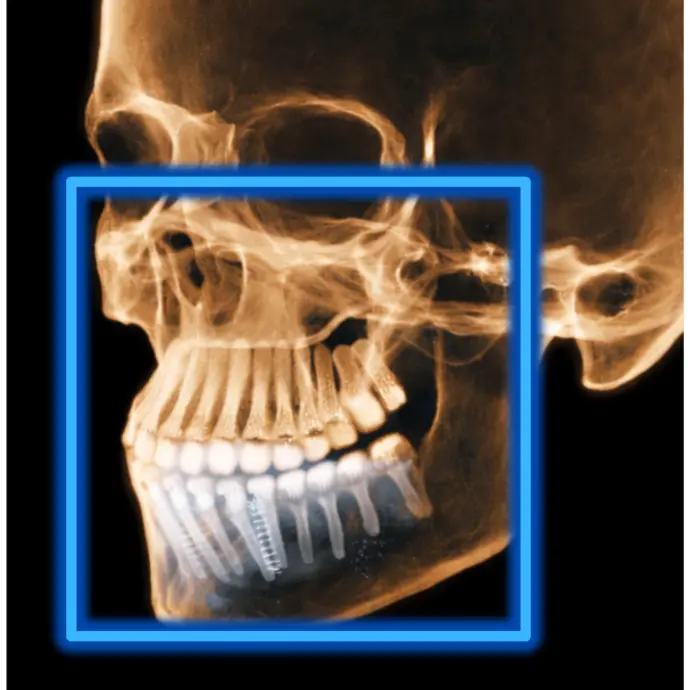

TOMOGRAFÍA DE IMPLANTES

Cuando es necesario evaluar las condiciones óseas de los rebordes alveolares.